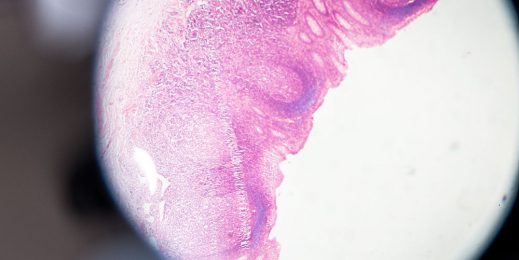

Легкая диагностика